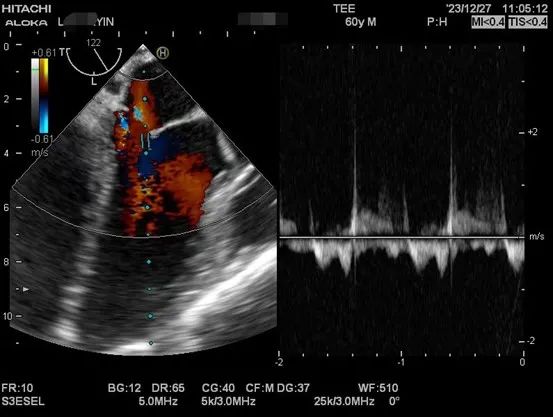

以下是肝移植术中TEE监测的图像。

肝硬化患者术前合并症较多,术中血流动力学波动剧烈,围术期可能发生严重低血压、心内血栓形成、肺栓塞、左室流出道梗阻、心室收缩舒张功能不全等危急事件,给麻醉管理带来巨大挑战。TEE是将超声探头放在食管中段或胃底,从心脏后方持续观察心脏结构和功能,避免肺气对成像的影响,图像清晰且不影响手术的操作,是肝移植术中重要的监测手段之一。美国心脏超声协会及美国心血管麻醉医师学会均推荐肝移植术中常规使用TEE。目前美国各大移植中心术中麻醉科术中常规使用TEE进行持续监测。